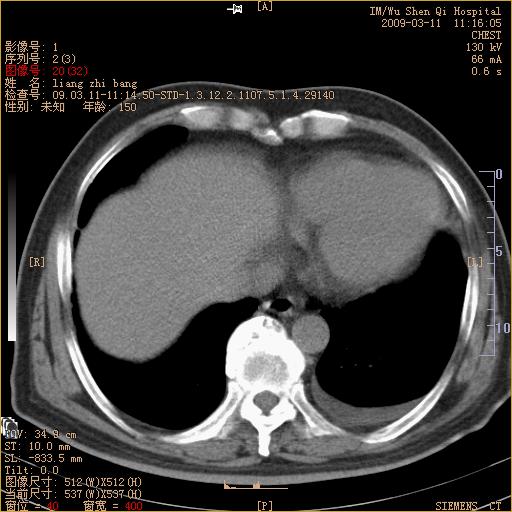

标题: CT18604:男,60岁,咳嗽一月余 [打印本页]

标题: CT18604:男,60岁,咳嗽一月余

1)考虑左肺上叶中央型肺癌并左肺上叶肺不张;建议必要时行纤支镜检查进一步明确诊断。2)左侧胸腔积液。

考虑左肺上叶中央型肺癌并左肺上叶肺不张

肺门肿块、支气管开口闭塞伴肺不张及胸水!典型的中心型肺癌变现!

1、左肺上叶中央型肺癌并上叶阻塞性肺不张。

2、左侧胸腔少量积液,右侧胸膜轻度增厚。

左肺们肿块并左肺上叶不张。考虑左肺中心性肺癌并左肺上叶不张及左侧胸腔积液